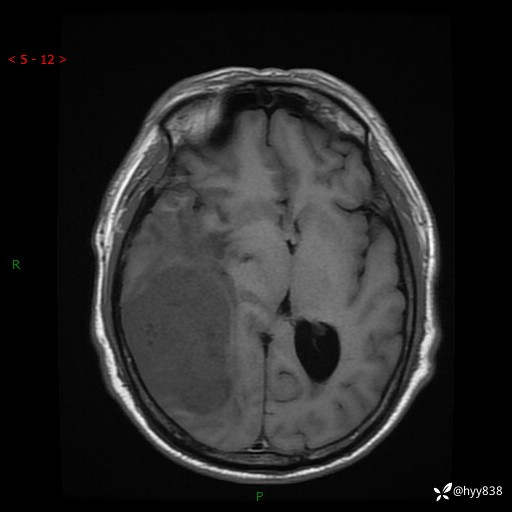

患者性别:男

患者年龄:56岁

简要病史:外院CT提示脑膜瘤,为进一步诊治来我院

临床诊断:颅脑占位

颅脑MRI平扫+增强